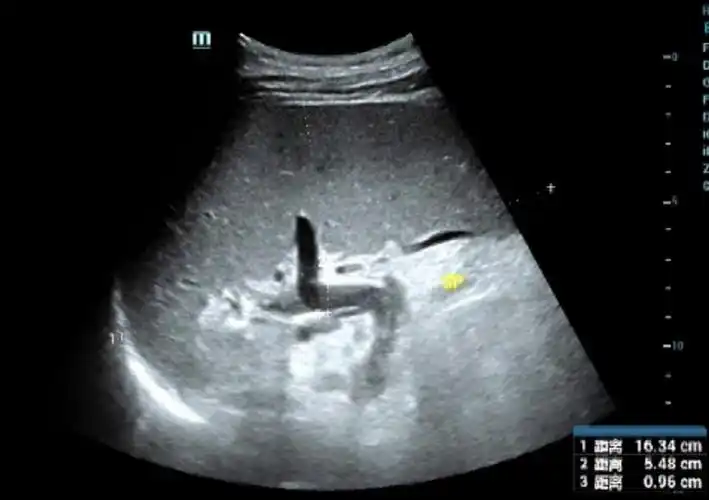

脾脏触诊 脾肿大的分度(深吸气时) 轻度:脾在肋下不超过3cm 中度:肋下

(胃泡鼓音区--traube区缩小消失) 增大不明显,侧位双手触诊 分度

5个肋单元(1个肋骨算1个肋单元,1个肋间隙也算一个肋单元)可以说脾大

脾大,有麻烦,三度划分要拿准

肝硬化脾大血小板低该怎么处理